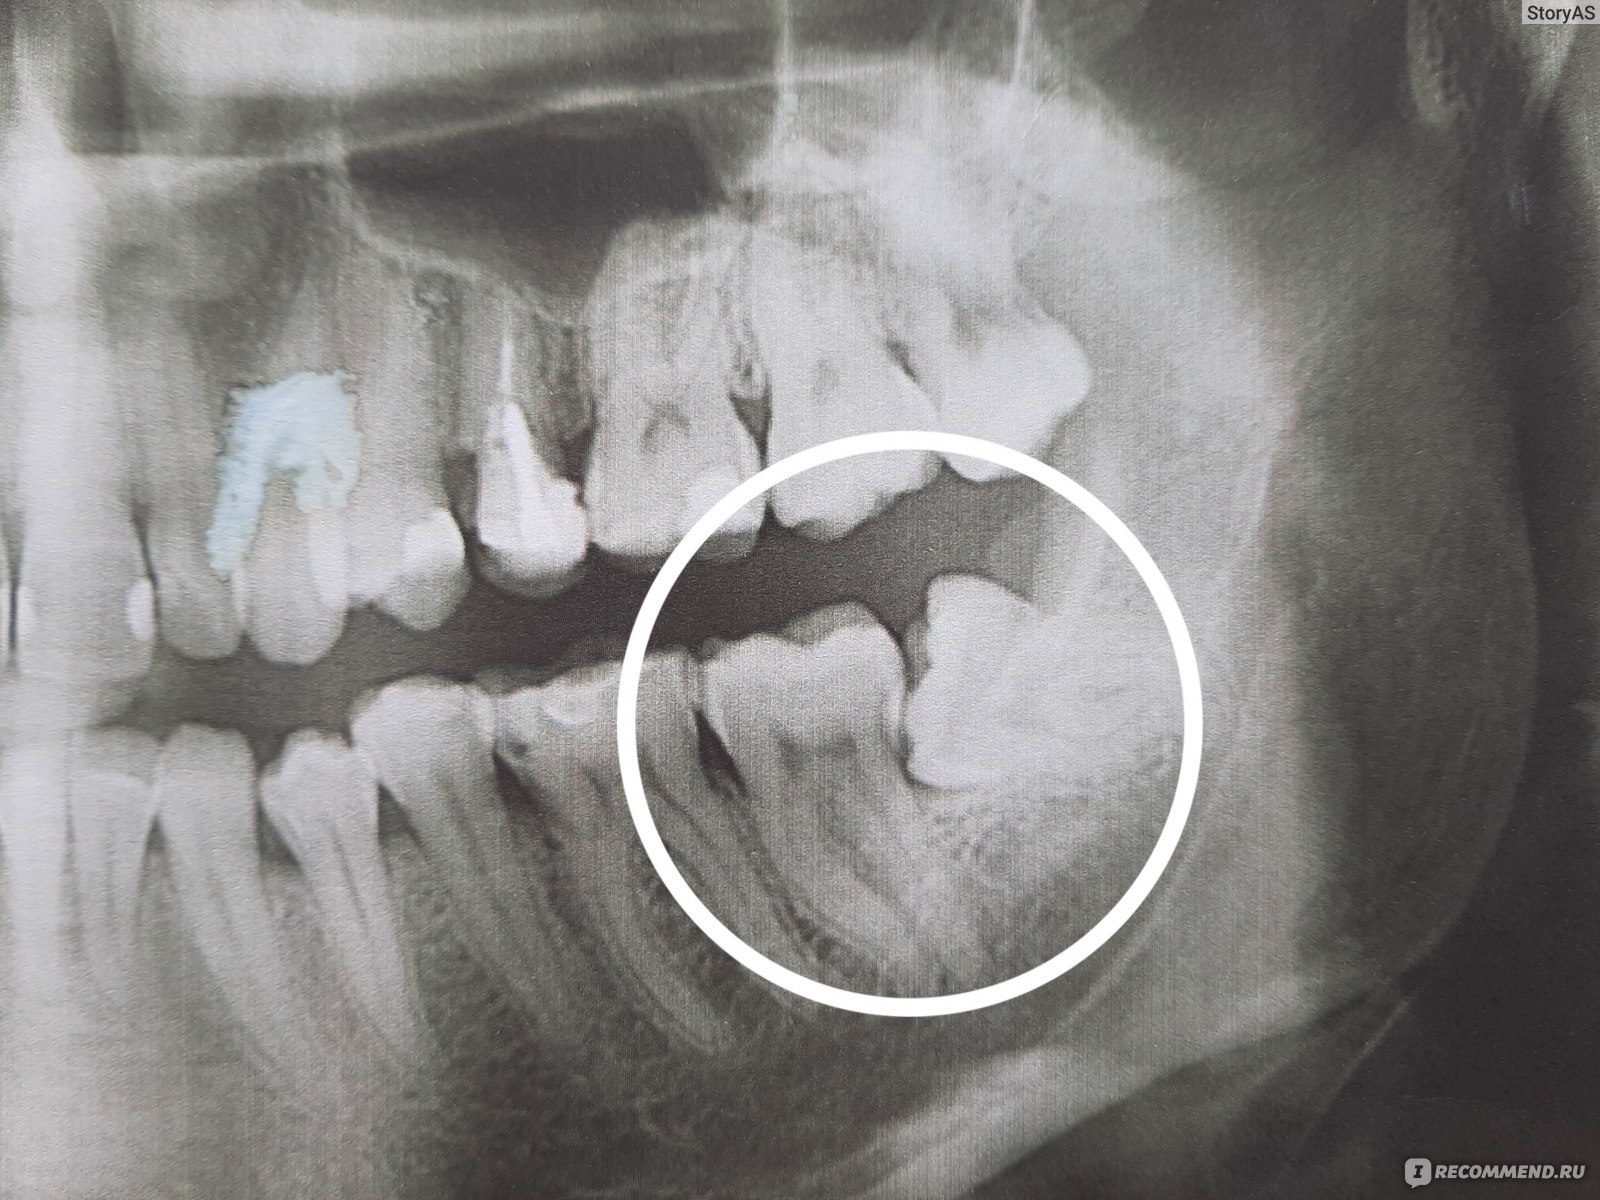

Дентальные снимки и диагностика кариеса